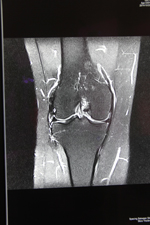

近期,我院今年新购的德国西门子MAGNETOM Avanto I-Class全身磁共振成像系统经过安装调适后正式投入使用。该系统为目前世界上最先进的1.5T磁共振,可以进行全身各部位的高质量扫描。该系统最突出的优势是:成像速度快、图像质量高,扫描覆盖范围大、扫描噪音小。患者在得到最快捷、最准确诊断的同时,还能享受到最舒适安静的检查。

该系统尤其在肿瘤诊断方面具有其突出的优势:一、个是分辨率好;二、反映的特性比较多,有利于临床把握肿瘤的诊断。三、它可以一次性的完成全身的核磁检查,第一次真正做到了高分辨的全身成像。可以很好的评估肿瘤的转移扩散程度,也通过全身的弥散成像使我们了解局部的淋巴结和全身的淋巴结,从其它医院完成的大量的病例来看,Avanto在全身肿瘤的筛查、评估方面准确性非常高。这为我院的肿瘤影像诊断提供了一个新的,有力的武器,为正常人进行磁共振全身疾病筛查带来福音。可真正做到对疾病早发现、早诊断、早治疗,使患者得到优质的医疗服务。